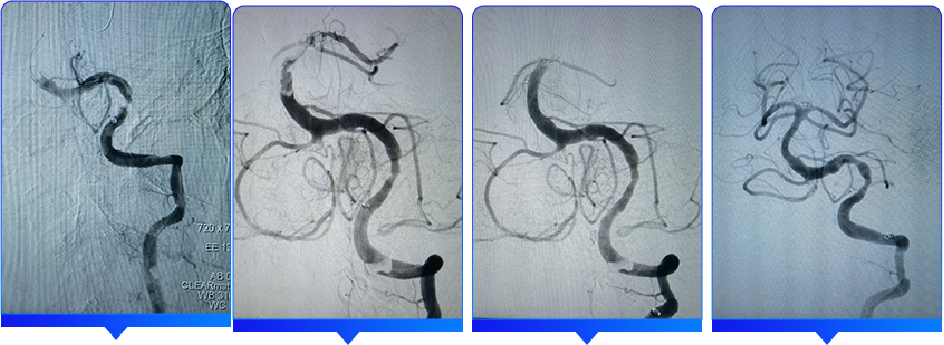

手术过程

采用seldinger穿刺法于右侧腹股沟下3cm处行股动脉穿刺,成功后置入8F动脉鞘。用5F猪尾巴造影管行主动脉弓上造影,为I型弓,两侧颈动脉显影良好,血流通畅,右侧椎动脉闭塞可能,左侧椎动脉血流缓慢。退出5F猪尾巴造影管后,利用泥鳅导丝置入5F单弯造影管分别置于双侧锁骨下动脉行选择性造影示:右侧椎动脉纤细,颅内段闭塞;左侧椎动脉为优势椎动脉,血流缓慢,V4段重度狭窄,狭窄约90%,基底动脉远端未显影,双侧大脑后动脉未显影。

退出单弯造影管,利用0.035in泥鳅导丝及单弯采用同轴技术将6F长鞘置于左侧椎动脉V2段,退出泥鳅导丝;置入0.014in微导丝和微导管在路图指引下缓慢通过左侧椎动脉狭窄处,微导管沿微导丝远端置于左侧大脑后动脉P2段,经微导管造影确认在血管真腔,利用300cm0.014微导丝交换退出微导管,沿微导丝置入3.0*20mm球囊在椎动脉狭窄段利用6atm预扩张;负压下沿球囊导管越过狭窄送入ACE抽吸导管,退出球囊导管,抽吸泵抽吸下抵近基底动脉闭塞近段,抽吸90s后缓慢回撤抽吸导管至体外,抽吸泵中可见多枚暗紫色血栓;复查造影:基底动脉中上段血栓影明显减少,基底动脉仍残留血栓;再次送入ACE抽吸导管至基底动脉近血栓处,抽吸约60s抽吸出多枚暗紫色血栓,继续抽吸120s,缓慢回撤抽吸导管至体外;复查造影:基底动脉完全再通,mTICI分级3级,远端未见栓塞及造影剂渗出;左侧椎动脉V4段残余狭窄约30%,观察5mm、10mm、30mm造影对比,狭窄处未见明显弹性回缩,血流维持良好。手术成功,退出6F长鞘。